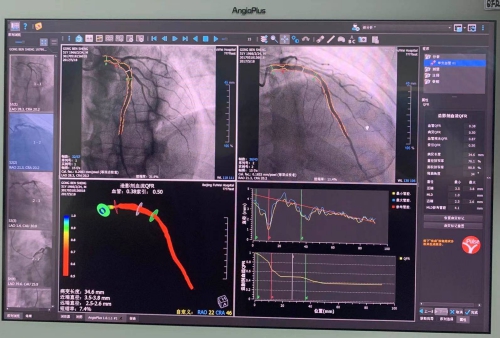

新一代AI QFR测量系统界面更简洁,操作更智能、计算更精准

第一代QFR测量结果界面

据心内科朱虹岷博士介绍,QFR是基于冠脉造影影像的无导丝FFR快速分析系统,第一代QFR测量基于两幅角度差大于25°的常规冠脉血管造影图像进行血管重建与血流分析,从而获得血流储备分数。新一代的AI QFR技术较前一代技术有很大改进,首先,在基于第一代QFR同源核心算法的基础上加入了人工智能算法,例如血流速度的计算,感兴趣血管段的选择,管腔轮廓勾画,分支计算等都融入了人工智能算法,大大简化了个人操作流程,也减少了个人操作误差,从而使得计算更精准,时间也更短;其次,新一代AI QFR可分别完成2D-QFR和3D-QFR测量,对于冠脉造影暴露清晰的病变,只需要一幅造影图像,在30秒内就能完成2D-QFR分析,计算精度超过93%;对于复杂病变可进行3D-QFR分析,需结合2个体位造影图像,1分钟左右即可完成分析,由于人工智能的辅助,因此较前一代QFR计算更准确;第三,基于造影的人工智能辅助全自动冠脉树无创FFR计算,是目前全球独家可进行分叉病变功能学分析的技术;最后,在AI QFR系统中,增加了微循环功能计算,从而完善了全冠脉系统的生理学功能评估。基于上述这些优点,相信未来QFR会有更广阔的应用前景。